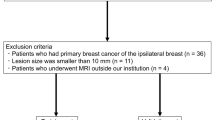

This single-center, retrospective case-control study was performed after institutional review board approval, with waiver of the informed consent requirement. The study was performed in compliance with the Health Insurance Portability and Accountability Act (HIPAA). A total of 56 patients who satisfied the inclusion criteria were retrospectively identified. To qualify, patients treated at our institution had to have pre-treatment MRI, and a histologically confirmed (from surgical excision and not from core needle biopsy) diagnosis of myxoma or myxofibrosarcoma between 01/01/2006 and 12/31/2017. Patients were excluded from the study if there was no pre-treatment MRI available, if the pre-treatment MRI was motion degraded or did not include a non-contrast enhanced T1-weighted MR imaging sequence, and a fluid-sensitive MR imaging sequence (STIR or T2-weighted sequence). Age and sex was recorded at the time of the histological diagnosis. The maximum size and location of the tumor was determined from evaluation of the pre-treatment MR study.